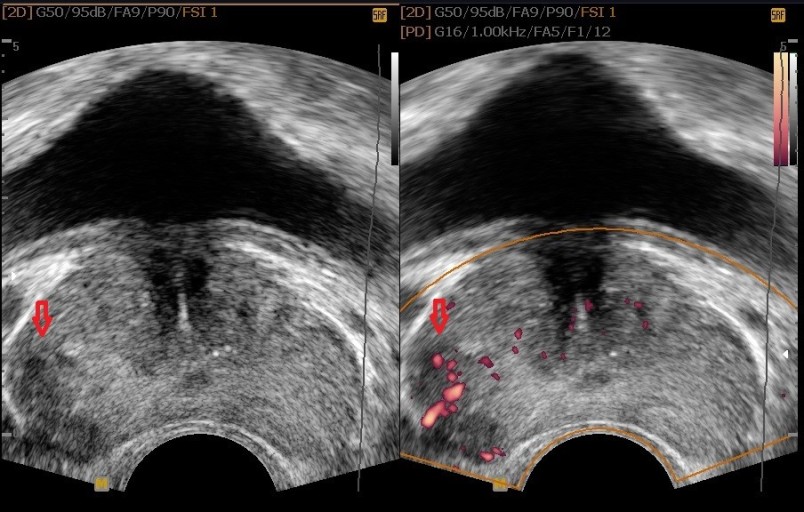

전립선암은 주로 전립선의 바깥쪽 부분인 말초대(Peripheral Zone)에서 발생합니다. 이 때문에 종양이 요도를 압박할 정도로 커지기 전까지는 증상이 나타나지 않는 경우가 많지만, 아래와 같은 비뇨기계 증상 및 전신 증상이 나타나기 시작하면 반드시 정밀 검사가 필요합니다.